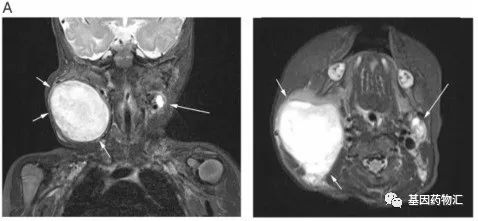

横纹肌肉瘤质子治疗,儿童肉瘤质子治疗给年轻父母带来无限希望横纹肌肉瘤质子治疗案例孩子承载着一个家的希望与未来,小孩病了,家长最担心,如果是癌症,更是毁灭性的打击。对于任何一个家庭来说,恍如经历世界末日也一点都不夸张。横纹肌肉瘤(RMS)是间质来源的一种恶性肿瘤,是儿童软组织肉瘤中最常见的一种,发病率次于恶性纤维组织细胞瘤和脂肪肉瘤。而3岁的Daisy Fai